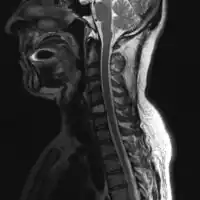

For SPB the most common presenting symptom is that of pain in the affected bone. Back pain and other consequences of the bone lesion may occur such as spinal cord compression or pathological fracture. Around 85% of extramedullary plasmacytoma presents within the upper respiratory tract mucosa, causing possible symptoms such as epistaxis, rhinorrhoea and nasal obstruction. In some tissues it may be found as a palpable mass.[3][4][5]

The diagnosis of plasmacytoma uses a diverse range of interdisciplinary techniques including serum protein electrophoresis, bone marrow biopsy, urine analysis for Bence Jones protein and complete blood count, plain film radiography, MRI and PET-CT.[6][7]

Skeletal surveys are used to ensure there are no other primary tumors within the axial skeleton. MRI can be used to assess tumor status and may be advantageous in detecting primary tumors that are not detected by plain film radiography. PET-CT may also be beneficial in detecting extramedullary tumours in individuals diagnosed with SPB. CT imaging may be better than plain film radiography for assessing bone damage.[6][7]